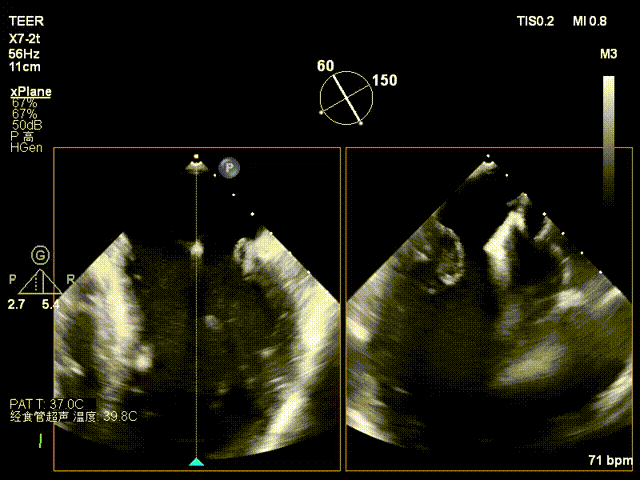

X-plane2区

X-plane2区彩色

X-plane 1区

X-plane 2区

X-plane 2区彩色